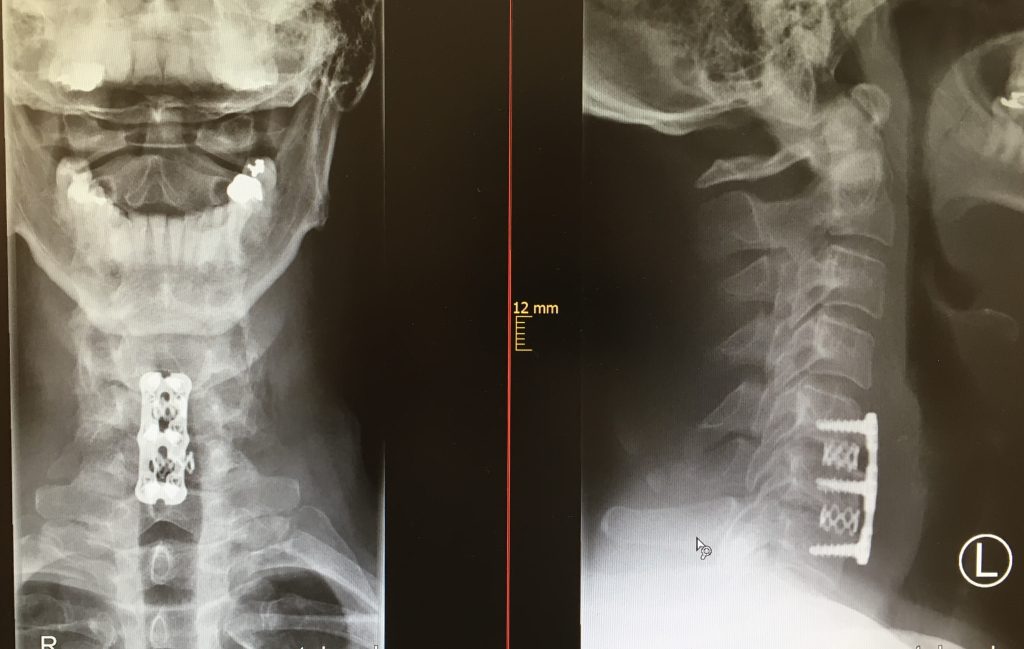

Puede realizarse por vía anterior o posterior, y en casos severos pueden combinarse las dos vías. La artrodesis cervical anterior es la más habitual y se realiza con una incisión en el flanco lateral anterior del cuello, y desde la misma se retiran los discos deteriorados y se descomprime la médula.

En algunos casos se necesita la retirada de un cuerpo vertebral. La sustitución de discos o cuerpo vertebral se realiza generalmente con implantes de soporte y placas atornillas. En casos muy seleccionados podría barajarse la sustitución con prótesis de disco cervical.